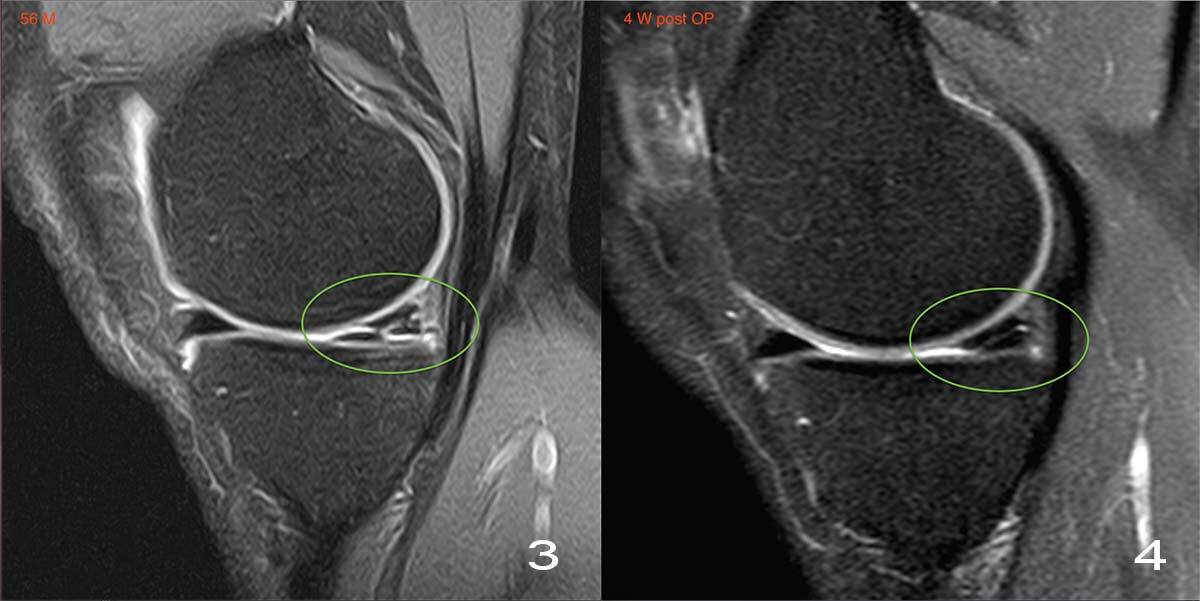

УЗИ - самый доступный и безопасный метод, саму кисту прекрасно видно.

МРТ, когда нужно заглянуть дальше, например, чтобы исключить повреждение заднего рога мениска или крестообразных связок - такие глубоко залегающие структуры по УЗИ не видно.

травмы - повреждение менисков (чаще задний рог медиального мениска), разрывы передней крестообразной связки.